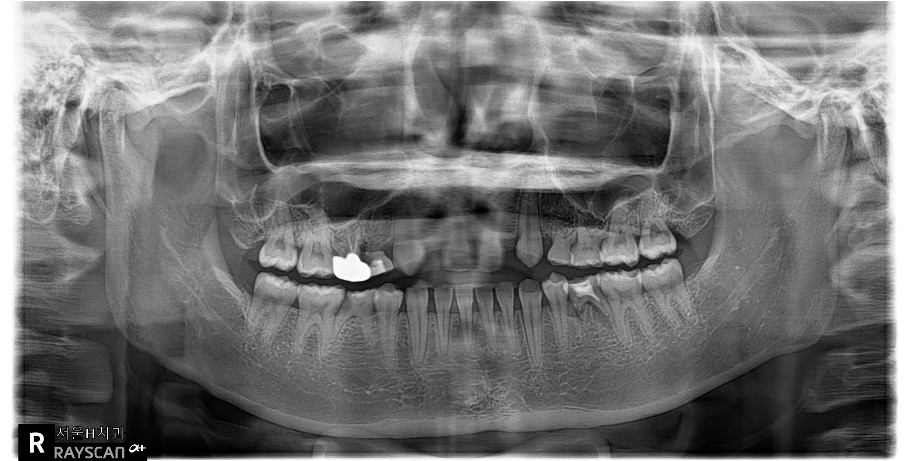

상기 환자의 경우 선천적 결손치부위인 12번과 22번의 공간은 교정으로 확보가 되어 있었으나 수술할 당시에 환자가 내원을 오랫동안 하지 않아 22번 공간에 약간의 relapse가 발생되어있는 상태였습니다.

양측 모두 처음에는 골이식없이 2.5직경의 onebody implant를 식립하였는데 22번의임플란트는 골유착 실패로 제거하게 되었습니다. 다시 마무리 교정을 한 후에 4개월 후 22번에 3.5직경의 임플란트를 골이식과 더불어 식립하였고 최종 보철물을 마무리하였습니다.

확실히 상악 전치부 동일부위에 2번의 수술을 진행하는 경우는 harmonic gingival line을 맞추는 것은 쉬운일이 아니라고 생각됩니다.